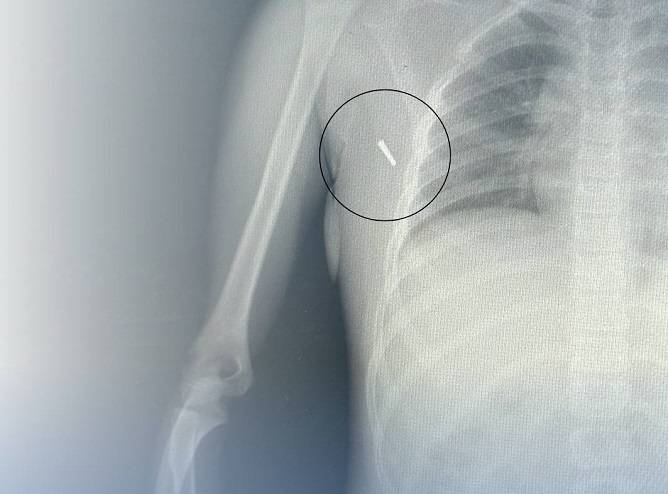

18 июля в вечернее время в приемное отделение стационара поступила 8-летняя девочка с травмой. Во время поездки на автомобиле у ребенка был установлен ртутный градусник для измерения температуры тела. В результате ДТП наконечник градусника отломился и вонзился в подмышечную впадину ребенка.

Наши травматологи успешно извлекли наконечник, провели контрольные анализы и рентген-снимок после изъятия, а затем оставили девочку на несколько дней в стационаре для наблюдения.